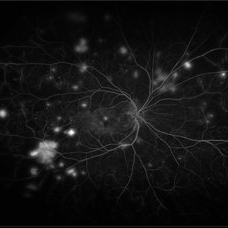

Von Hippel-Lindau Syndrome with Retinal Hemangiomas

May 30 2017 by Olivia Rainey

Ultra-wide-field fluorescein angiogram of the left eye of an 29-year-old female with multiple retinal hemangiomas secondary to Von Hippel-Lindau Syndrome.

Photographer: Olivia Rainey

Imaging device: Optos California

Condition/keywords: fluorescein angiogram (FA), fluorescein leakage, left eye, Optos, retinal hemangioma, ultra-wide field imaging, Von Hippel-Lindau